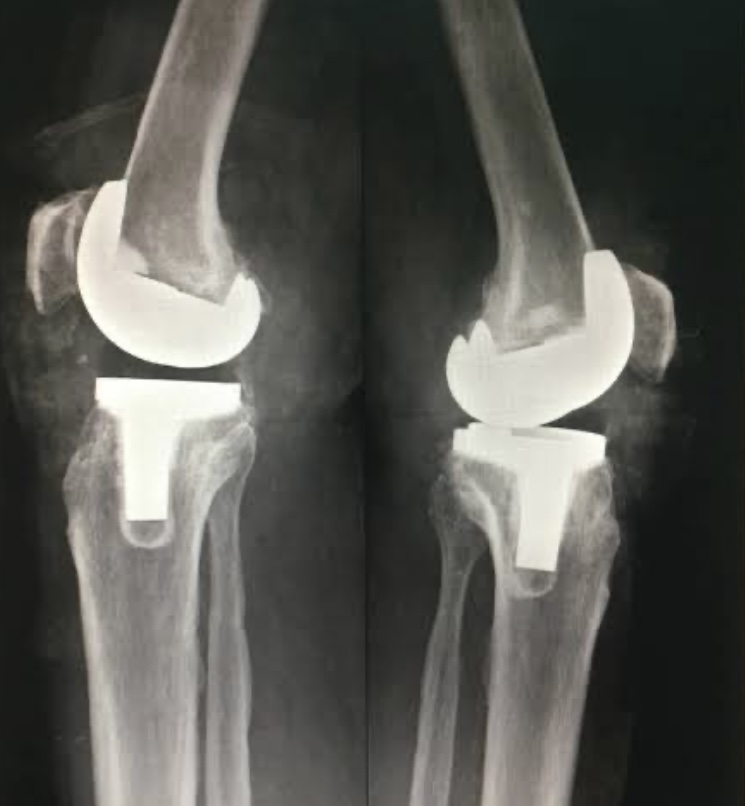

How a knee joint looks after total knee replacement